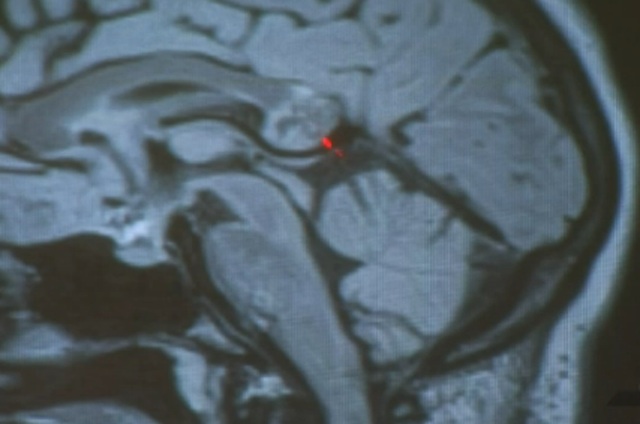

While we've seen enough horror movies about evil twins, truth is still stranger than fiction. A 26-year-old woman had a shocking and freaky revelation when doctors told her that the brain tumor she thought she had turned out to be her embryonic twin. The chilling part is that it had bone, hair and teeth.

Yamini Karanam, an Indiana University Ph.D. student, went to doctors after she started noticing that she had problems understanding what she was listening to and reading, NBC Los Angeles reports. After consulting with neurologists and neurosurgeons who couldn't agree what was causing her medical issues, she reached out to Dr. Hrayr Shahinian at the Skullbase Institute in Los Angeles.

Shahinian thought she had a brain tumor and scheduled a surgery to remove it. One of Karanam's friends even set up a crowdsourced fundraiser to help pay for the surgery.